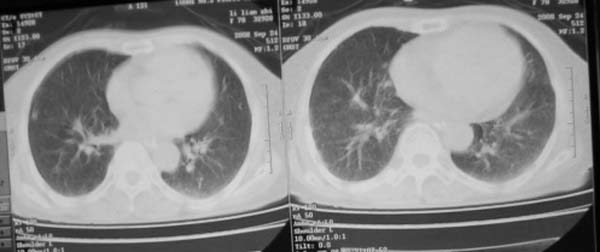

女,78岁,声嘶月余,否认有既往病史,有粉尘接触史10年。

颈部见多枚淋巴结肿大,考虑尘肺继发结核,喉部淋巴结钙化,不除外喉部慢性淋巴结炎、喉淀粉样变及类癌等

肺癌伴纵膈、双颈部淋巴结转移;尘肺。

双上肺结节融合影,周围有纤维条索影,结合粉尘接触史,首先考虑尘肺。双侧颈部有增大淋巴结,有声嘶表现,肺癌淋巴结转移不能排除。可结合颈部淋巴结活检。